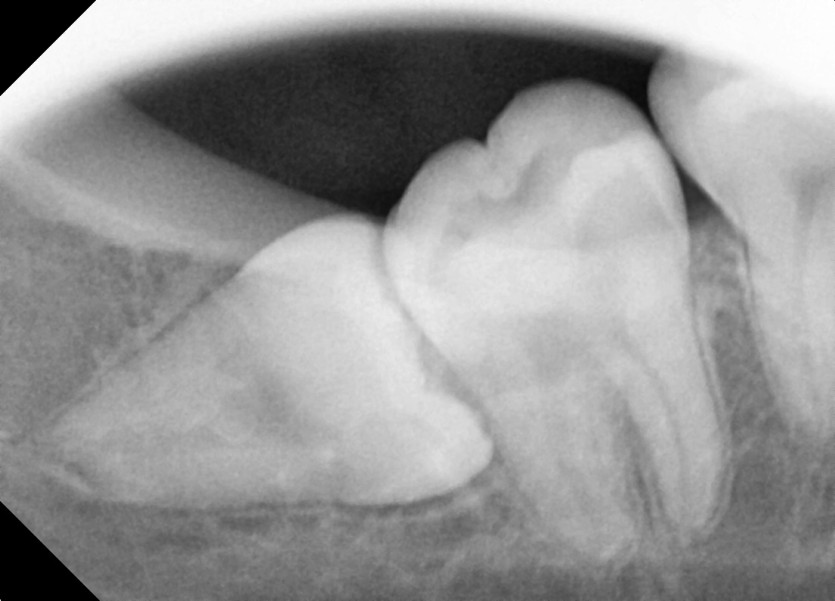

#18,28,38,48 사랑니 발치

구강 외과 전문의가 당일 발치했습니다.